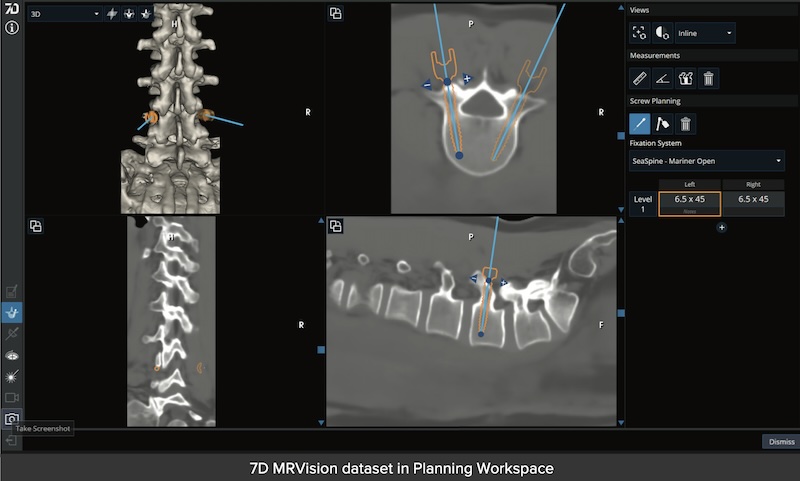

The Orthofix-SeaSpine 7D FLASH Navigation system is a comprehensive and flexible system that is imaging agnostic and provides several unique options for spinal and cranial navigation. The system utilizes Machine-vision that uses structured light and software to deliver registration in less than 30 second. It is utilized in cranial, spinal, percutaneous procedures. Also features MRIVision which is proprietary software that utilizes a special MRI sequence to render a synthetic CT from MRI making it possible to complete with no radiation.

• MRIVision Module:

• Utilizes a specialized MRI sequence acquired preoperatively to produce a synthetic CT image which can be used to perform intraoperative FLASH for instant registration.